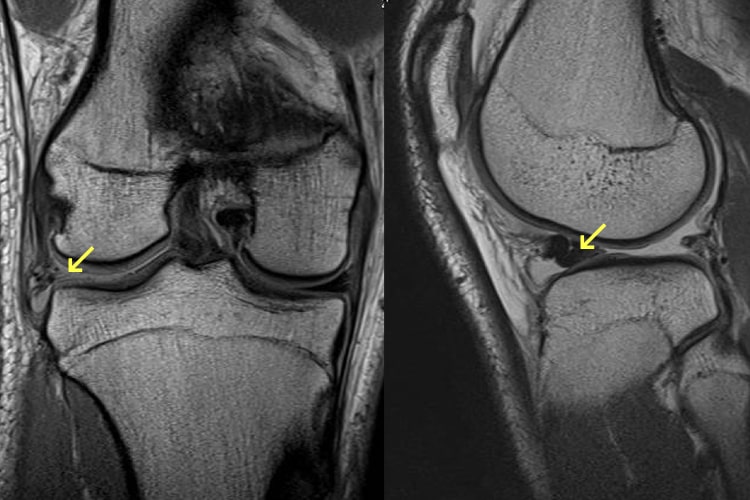

半月板損傷

半月板損傷は膝関節の屈伸と回旋との協調運動が破綻した時に発生します。原因はスポーツ外傷によるものが多く、その他では転倒、捻挫、交通事故等があります。損傷によって、膝の曲げ伸ばしの際に痛みやひっかかりを感じたりします。ひどい場合には、膝に水(関節液)がたまったり、急に膝が動かなくなる“ロッキング”という状態になり、歩けなくなるほど痛くなります。治療としてはリハビリテーション療法、膝サポーター、ステロイド、ヒアルロン酸の関節内注射等、保存的治療での症状改善を目指します。保存的治療で改善しない場合には手術を行います。手術法には切除術(損傷した部分を切り取る)と縫合術(損傷した部分を縫い合わせる)の2種類があり、症状に合わせて選択します。